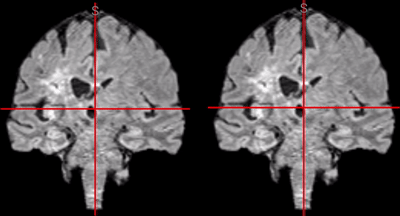

nv.get_volume_data ( x1, x2, y1, y2, z1, z2 )

maybe?

endless processing possibilities :)

nv.set_volume_data ( x1, x2, y1, y2, z1, z2, new data )

nv.set_label_data ( x1, x2, y1, y2, z1, z2, new data )

nv.get_label_data ( x1, x2, y1, y2, z1, z2 )

Goal: Nobrainer models as Boostlet!

Satra Ghosh's Senseable Intelligence Group

ROI Selection

Shruti Varade

all different!

soon in Boostlet.js!